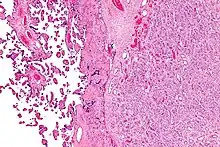

Micrograph of a chorangioma (right of image) and normal placenta (left of image); H&E stain.

Histologically, chorioangiomas consist of abundant vascular channels and may be cellular.